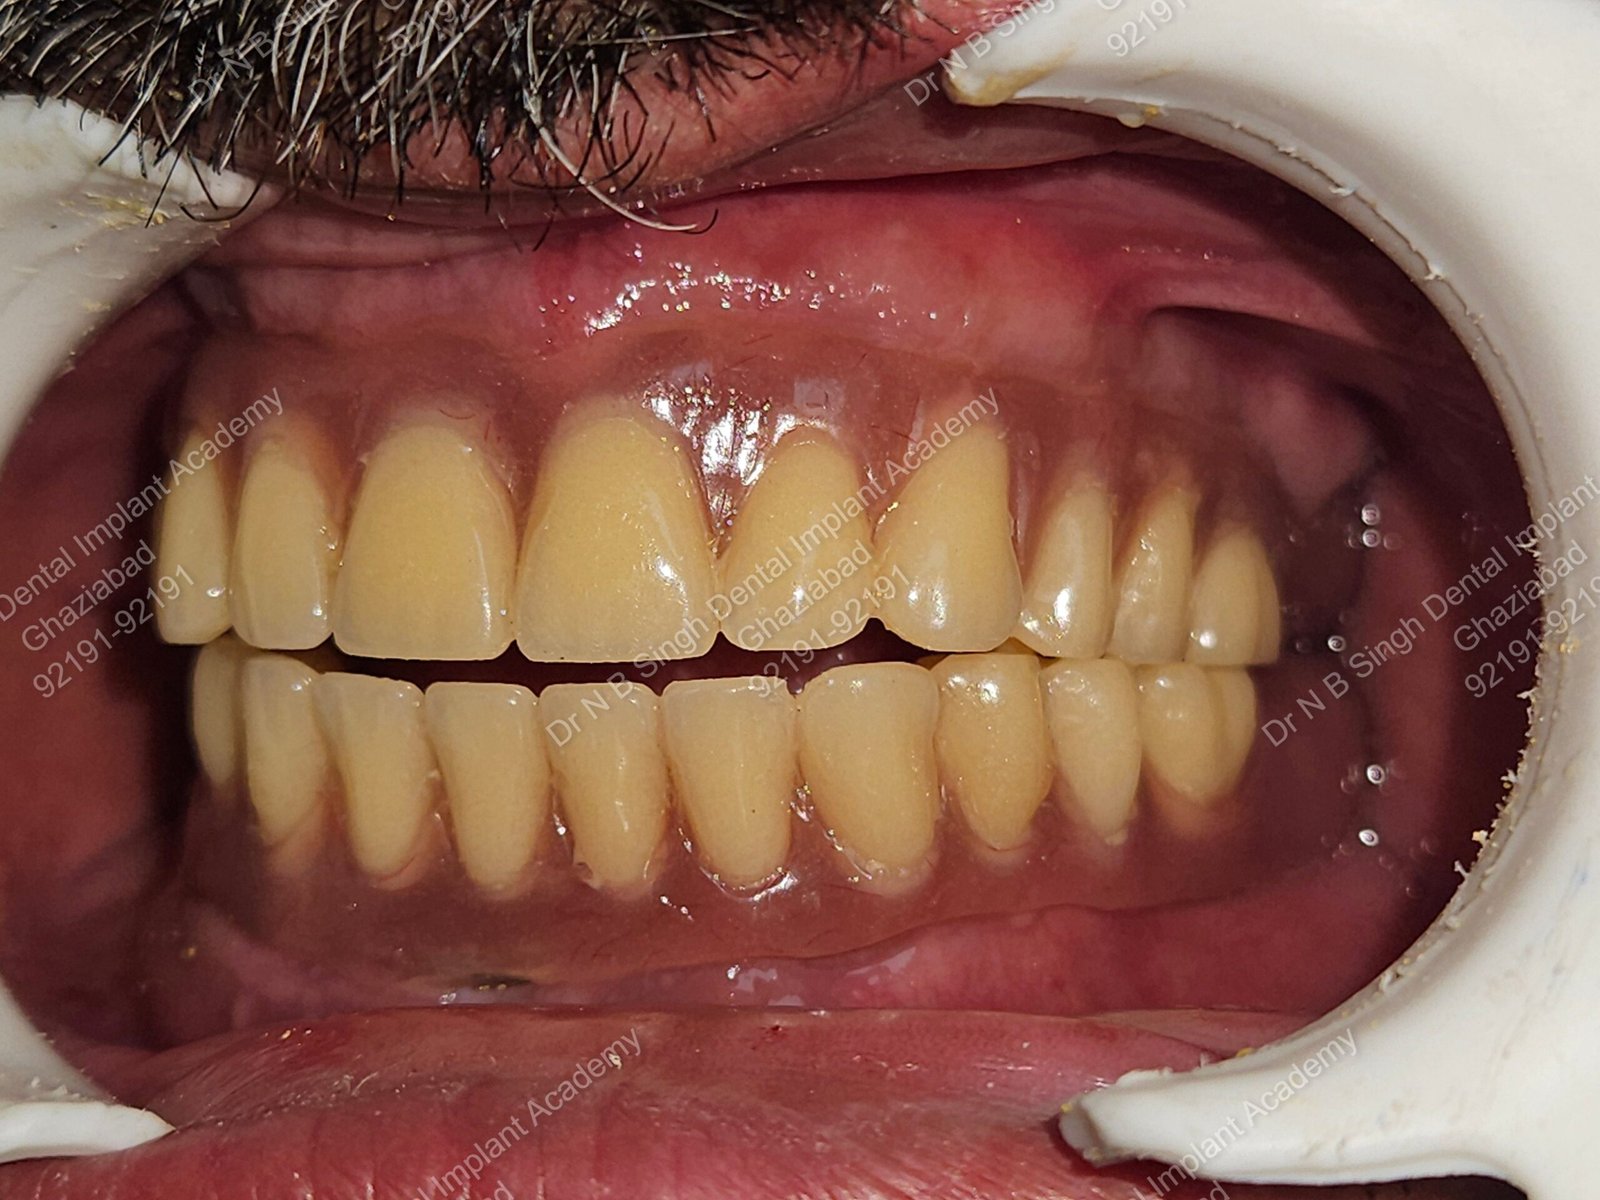

1006 Basal implant full mouth-DEEPAK